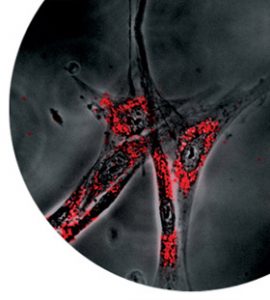

また、そのアクリル樹脂の突起間距離を100nm程度にし、その隙間にレクチン(エイズウイルスや赤血球、白血球を吸着させる物質)を塗っておくことで、 大きな物質(赤血球や白血球)は除外し、100nmのエイズウイルスだけを取り去ることが可能となります。血液製剤などのウイルスを予め取り去ることに よって、これによる感染を未然に防ぐことも可能となるでしょう。

ウイルスの形態と生態の研究、ナノテクノロジーによる摸倣創製と物性の研究。両者の素晴らしい出会いが、ナノ粒子が集まってつくる中空の球に、抗がん剤な どの薬品を閉じ込める薬物除法担体(DDS)の開発、血液製剤に混入したエイズウイルスの除去技術などに結実しようとしているのです。

金平糖型の人工ウイルスを水へ入れ、それを冷凍し乾燥させると、凍って体積が大きくなった水は、ウイルスを押し出します。それらは、互いに集まり、突起が 歯車のように噛み合って、中空の球体ができることが発見されました。この内部に薬などを閉じ込めることで、DDSに利用できるのではないかと、更に実用に 向け研究が行われています。ウイルス型粒子は、物性の解明とともに、次世代の医療に役立つものづくりにも大きく貢献していくことでしょう。